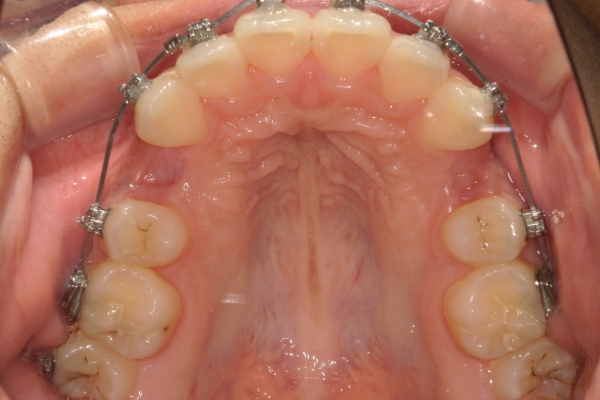

PROCESS

半年

上顎前歯が1cm近く前方に出ており、叢生を改善しつつ前歯を大きく引っ込めるために上下顎小臼歯の抜歯が必要と診断しました。治療後は、主訴であった前歯の突出と奥歯の噛み合わせのずれが改善され、上下の咬合関係が安定しました。